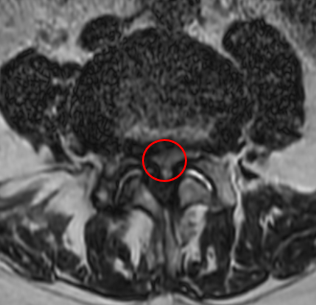

治療前

腰椎MRIの画像を確認したところ、赤い枠内のL4/5で脊柱管が狭窄しているのを確認しました。また「歩いて5分程度でより痛くなる」というお話しから間欠性跛行の症状が出ていると考えられます。

これらから、痛みの原因はL4/5部分の脊柱管狭窄症だと診断しました。